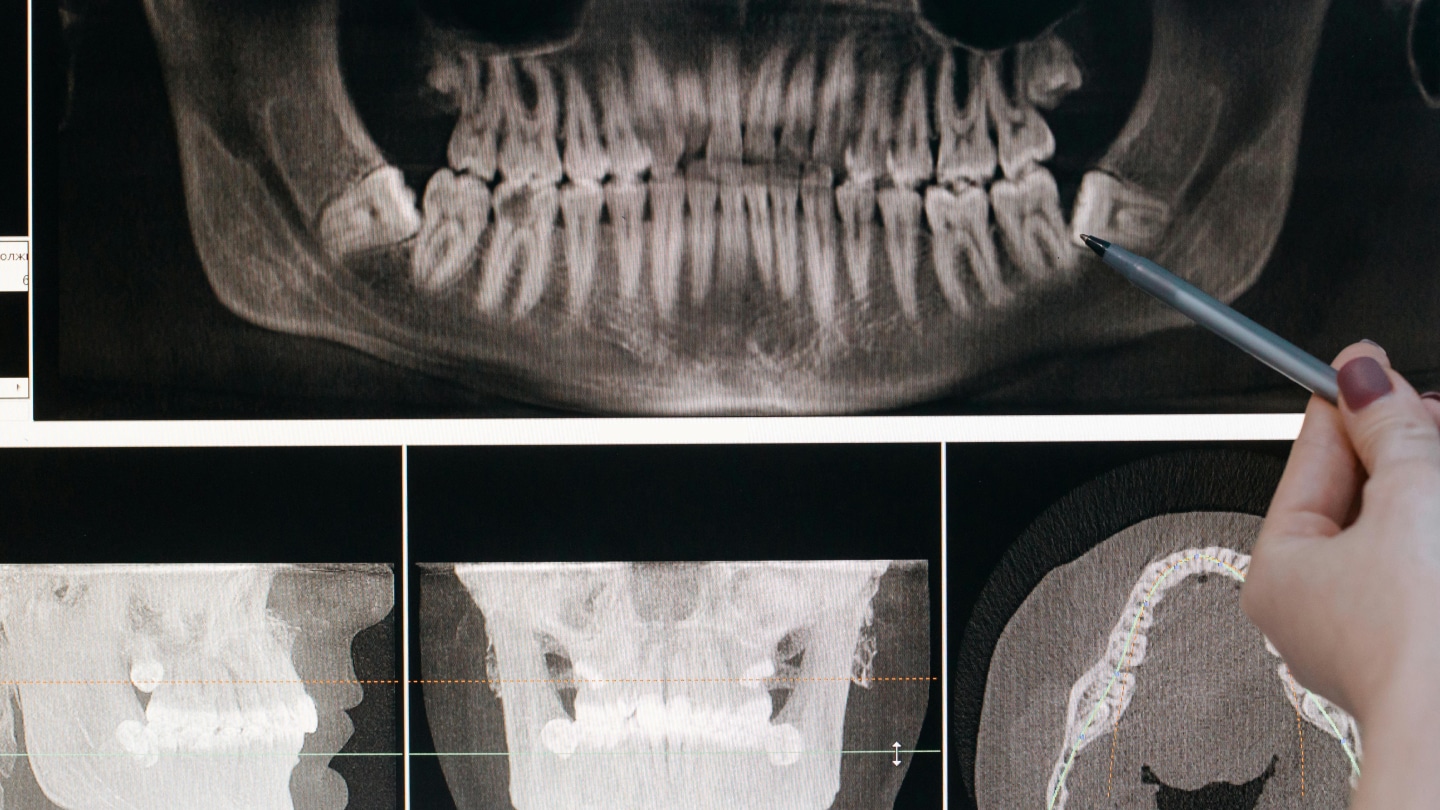

При бруксизме обычно обращаются к стоматологу, гнатологу или ортодонту. Для поиска причин, связанных с нервной системой — к неврологу. Если вы подозреваете у себя бруксизм, врач может:

- изучить состояние зубов на предмет износа;

- оценить жалобы на боль и дискомфорт;

- направить на исследование сна (полисомнография), если есть подозрение на нарушения.